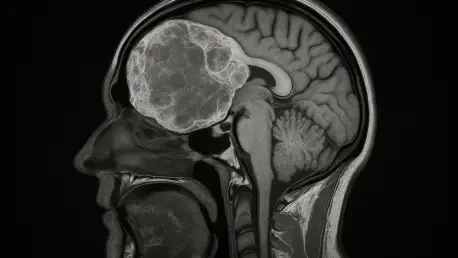

Distinguishing between general autism and cerebral folate deficiency (CFD) with “autistic features” is a complex diagnostic challenge because the behavioral symptoms can look nearly identical on the surface. The FDA has been very clear that Wellcovorin is approved specifically for CFD in patients with confirmed genetic variants, which makes genetic testing the non-negotiable gatekeeper for this treatment. We have to move beyond behavioral observation and into molecular diagnostics to ensure we are targeting the actual blockage that affects folate transport into the brain. Without these specific diagnostic protocols, we risk a “shotgun approach” to prescribing that could lead to widespread use in the broader autism community where the drug may provide no benefit. Precision medicine is the only way to navigate these overlapping symptoms responsibly, ensuring the drug reaches the less than 50 people it was truly intended for.